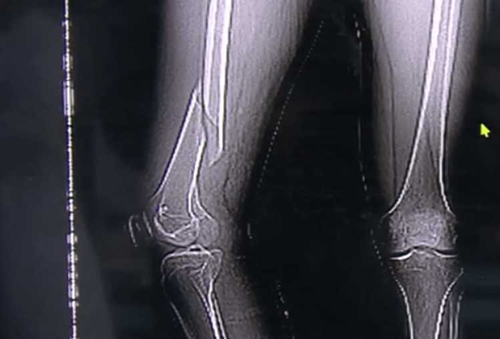

| Chân của anh Vương gãy vì ham mê tập Yoga quá độ. |

Ngay lúc sau, anh nghe thấy một chiếc "cạch" rồi đau nhói ở đùi. Biết đã xảy ra sự cố, anh Vương nén đau vội vàng đến bệnh viện điều trị. Qua kiểm tra, bác sĩ phát hiện xương đùi của anh Vương bị gãy và có rất nhiều huyết khối ở chi dưới.